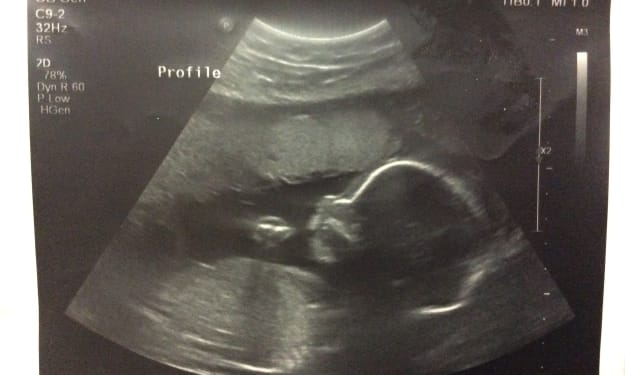

To My Child

To my child who is not yet born: there are many things that I wish for you now and on every single day after your arrival. Yet, life is not easy and the people in this world make it so much more difficult, but I wish you a good heart and soul. I am not a saint, which you will come to realize that I am not perfect and I will make many mistakes. However, I wish that you are stronger and distinguish right from wrong. As you grow, you will realize the little that we have, but my wish for you is that you realize family and love is the only thing that matters. My baby boy, I am very scared that I will do something that causes you sadness or pain. My wish for you is to understand that I’m only doing the best that I can. My tiny love, you are the greatest little thing to ever happen to me after twenty two years. Having you within me is a true gift from God. I truly wish you do best by us both. My child the world is a great adventure, but with every adventure comes danger so always protect yourself. I hope and really wish that you become a great man that protects, loves, cherishes and enjoys his family. No one is perfect, not on this Earth, not I, not your dad, and definitely not our families. Always and always remember that just because they’re family doesn’t mean that they have the right to hurt you. My baby, this world is full of love and great people and those that are the opposite, my dear please don’t lock your heart away after one heartache, for that can be rather painful.